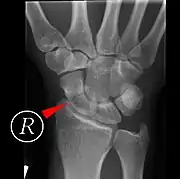

Scaphoid fracture before and after operation

Fractures of the scaphoid are the most common of the carpal bone injuries, because of its connections with the two rows of carpal bones.[1]:177

The scaphoid can be slow to heal because of the limited circulation to the bone. Fractures of the scaphoid must be recognized and treated quickly, as prompt treatment by immobilization or surgical fixation increases the likelihood of the bone healing in anatomic alignment, thus avoiding mal-union or non-union.[6] Delays may compromise healing. Failure of the fracture to heal ("non-union") will lead to post-traumatic osteoarthritis of the carpus.[1]:189 One reason for this is because of the "tenuous" blood supply to the proximal segment.[3] Even rapidly immobilized fractures may require surgical treatment, including use of a headless compression screw such as the Herbert screw to bind the two halves together.

Scaphoid fractures may be difficult to diagnose via plain x-ray. A repeat x-ray may be required at a later date, as might cross-sectional imaging via MRI or CT scan.[6]